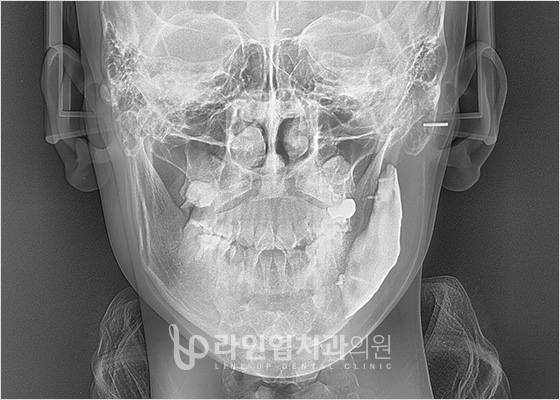

前后照片

Before

After